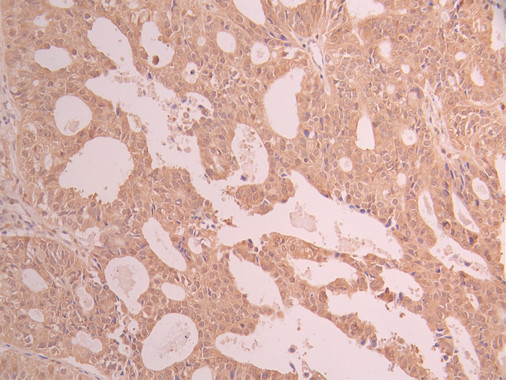

IHC image of CSB-RA546399A0HU diluted at 1:100 and staining in paraffin-embedded human ovarian cancer performed on a Leica BondTM system. After dewaxing and hydration, antigen retrieval was mediated by high pressure in a citrate buffer (pH 6.0). Section was blocked with 10% normal goat serum 30min at RT. Then primary antibody (1% BSA) was incubated at 4°C overnight. The primary is detected by a Goat anti-rabbit polymer IgG labeled by HRP and visualized using 0.05% DAB.